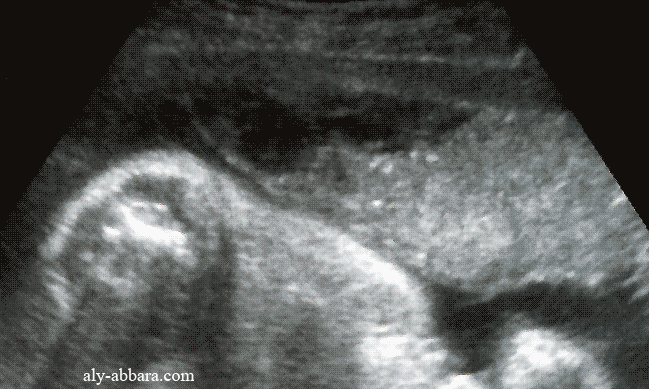

Hématome rétroplacentaire marginal à 29 semaines d'aménorrhée

• Cette image échographique montre un hématome rétroplacentaire décidual basal latéral avec décollement marginal du disque placentaire sur une longueur maximale de 50 mm et le décollement partiel des membranes amniotiques avoisinant(amnios et chorion).

• Cliniquement : la survenue brutale de métrorragie importante à 29 semaines d'aménorrhée suivie par l'apparition d'une hypercontractilité et d'une hypertonie utérines. Pas d'anomalies du RCF (rythme cardiaque fœtal).

Naissance par césarienne, en urgence, d'un enfant criant aussitôt et pesant 1320 g.